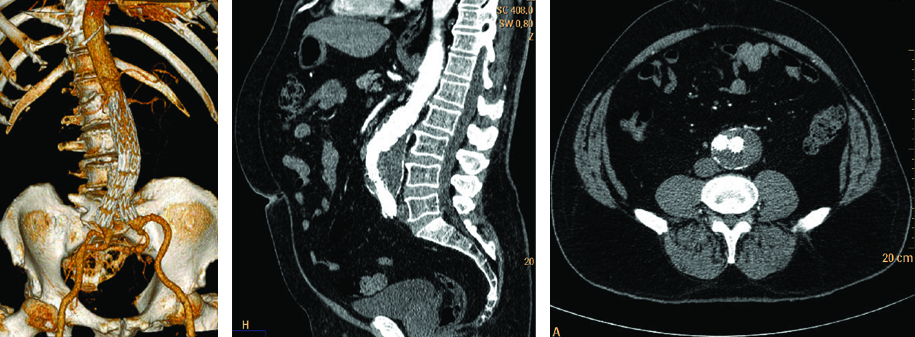

La Ecografía es el método de elección para el diagnóstico inicial, no solo por su amplia disponibilidad sino porque permite rápidamente la realización de mediciones en el plano longitudinal, anteroposterior y transverso (Fig. 26). Está indicada para la realización del screening del aneurisma de aorta abdominal en pacientes mayores de 65 años y con factores de riesgo.

La técnica de evaluación del aneurisma de aorta abdominal incluye mediciones, las cuales deben realizarse desde los bordes externos de la misma. En el plano longitudinal se examina la aorta desde el diafragma hasta la bifurcación ilíaca, y se miden el diámetro anteroposterior y la longitud del aneurisma. En el plano axial se mide el diámetro transverso. Para categorizar el tipo de aneurisma se examina la relación y distancia del aneurisma con respecto a la emergencia de la arteria mesentérica superior, de las renales y de la bifurcación ilíaca. Se examinan las arterias ilíacas y se mide su diámetro para determinar si están comprometidas. Las arterias ilíacas primitivas tienen un diámetro anteroposterior normal de hasta 11 mm (Fig 27).

El DC permite una evaluación más exhaustiva, con la cual no solo podemos determinar con precisión los límites de la dilatación aneurismática sino que también hace posible percibir la turbulencia en el flujo dentro de la misma (Fig. 28).

Al realizar la evaluación ecográfica, el especialista no debe dejar pasar por alto la presencia de trombosis mural o trombos de flotación libre en su informe, lo cual en una segunda etapa estará íntimamente relacionado con el abordaje terapéutico del paciente (Fig. 29).

Se debe tener en cuenta la posible asociación entre los aneurismas de la aorta abdominal y aquellos presentes en las arterias ilíacas, torácicos, femorales y poplíteos (Fig. 30), los cuales ocurren en un 50%, 12% y 15% de los casos, respectivamente (20).

Luego de la evaluación ultrasonográfica inicial podemos optar por diferentes métodos de diagnóstico por mágenes de manera tal de ampliar el algoritmo diagnóstico y tener una visión más amplia de esta patología. La Angio TC helicoidal, con contraste, es el segundo paso y pre quirúrgico que permitirá no solo realizar una evaluación multiplanar del paciente sino también generar reconstrucciones tridimensionales y así obtener una representación más anatómica de los elementos vasculares (Fig. 31).

Este método de diagnóstico nos permite medir el aneurisma en los planos axial, coronal y sagital, evaluando su cuello y relación con las arterias renales; es indispensable para planear el tratamiento endovascular.

En cuanto a la Angio Resonancia con gadolinio, permite una óptima visualización de la morfología del aneurisma, sus angulaciones y tortuosidades, así como también identificar bien los vasos renales y viscerales. Es importante mencionar que, a diferencia de la Angio TC, en este caso la Resonancia no utiliza radiaciones ionizantes ni contrastes iodados endovenosos. La desventaja es que no logra una buena definición del diámetro transverso del cuello ni de las arterias ilíacas (Fig. 32).

La Arteriografía es el método indicado en aquellos casos en los cuales el aneurisma se encuentra asociado a enfermedad oclusiva ilíaco-femoral, afectación de los vasos viscerales (angina abdominal) o sospecha de enfermedad vascular renal (hipertensión renovascular o falla renal inexplicable) (Fig. 33).